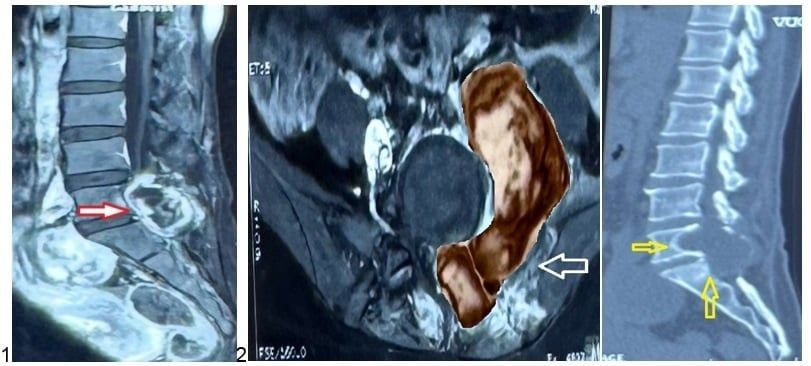

Kết quả chụp MRI cho thấy khối u kích thước lớn xâm lấn các cấu trúc lân cận và gây hủy xương vùng cột sống cùng

BS CKII Lê Điền Sơn - Phó trưởng Khoa Ngoại Thần kinh, Bệnh viện Nhân dân 115 - chia sẻ: "Khối u nằm đúng vị trí phẫu thuật cũ, có hình ảnh phát triển bất thường. Do đó, chúng tôi nghĩ nhiều đến khả năng u tái phát, thậm chí có thể mang tính chất ác tính".

Kết quả phẫu thuật cho thấy khối u là u bao dây thần kinh ngoại biên ác tính (MPNST – Malignant Peripheral Nerve Sheath Tumor). Hiện chị L. đang được theo dõi và điều trị bổ sung bằng hoá xạ trị theo phác đồ phù hợp.